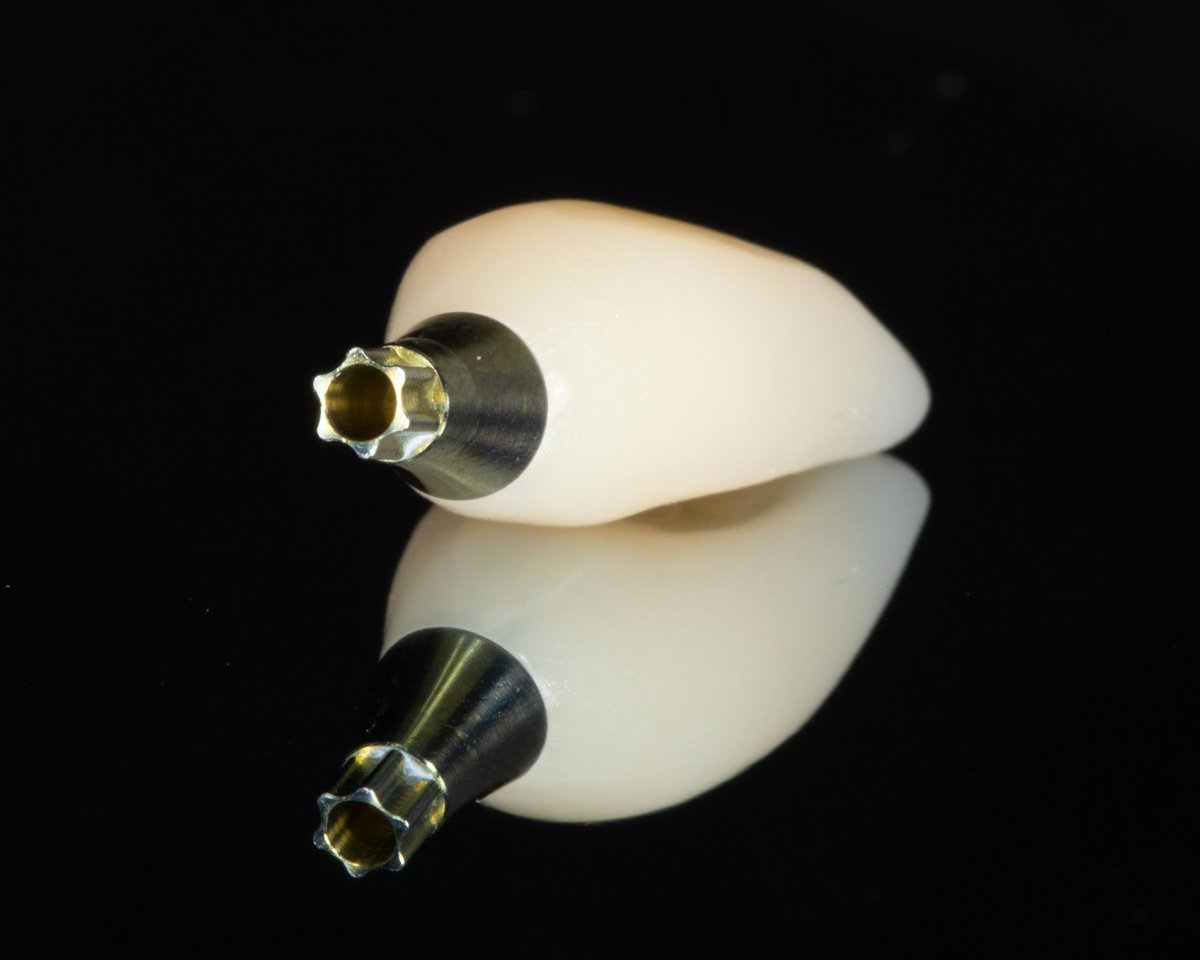

Hallmark Dental Laboratory Ltd. is a full-service dental lab that provides services to dentists across Canada. We specialize from dentures to crown & digital